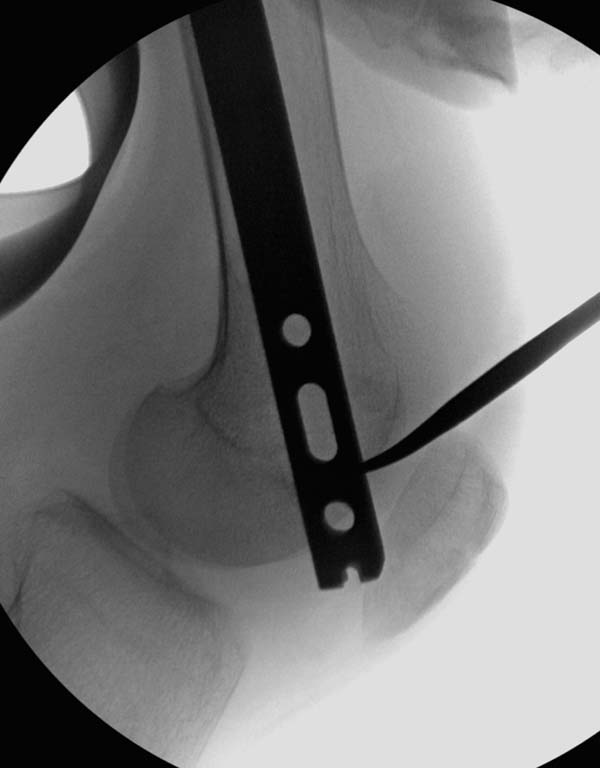

остаться до конца лечения, начал изучать язык... Для облегчения

транспортировки на второй день после поступления правая сторона была

фиксирована ретроградным гвоздем.

Теперь по серьезному. Учитывая качество кости и низкий гемоглобин,

периодический гемодиализ и воодушевленный результатом выступлении

Челнокова, вместо пластины решил попробовать гвоздь. Но жесткие FDА

условии не позволяют воспользоваться дивайсом до получения разрешения на